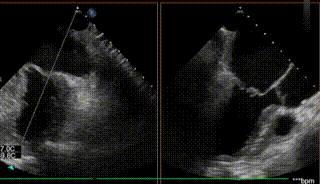

【二尖瓣相关参数】二尖瓣关闭时P2P3呈弓形脱入左房。二尖瓣后叶脱垂并重度偏心性反流(原发性:Carpentier II型,缩流颈8.3mm,反流面积0.42cm²,反流容积71ml);P2+P3区脱垂,脱垂范围约14×10mm,前叶2偏3区瓣体长度:25mm,后叶2偏3区瓣体长度:19mm;MVA:6.33cm²。左房内径47mm,左室60/39mm。

图1-4. 术前在交界、左室长轴切面及3D视角下可见大量二尖瓣反流,反流区宽,MultiVue下可见P2-P3脱垂